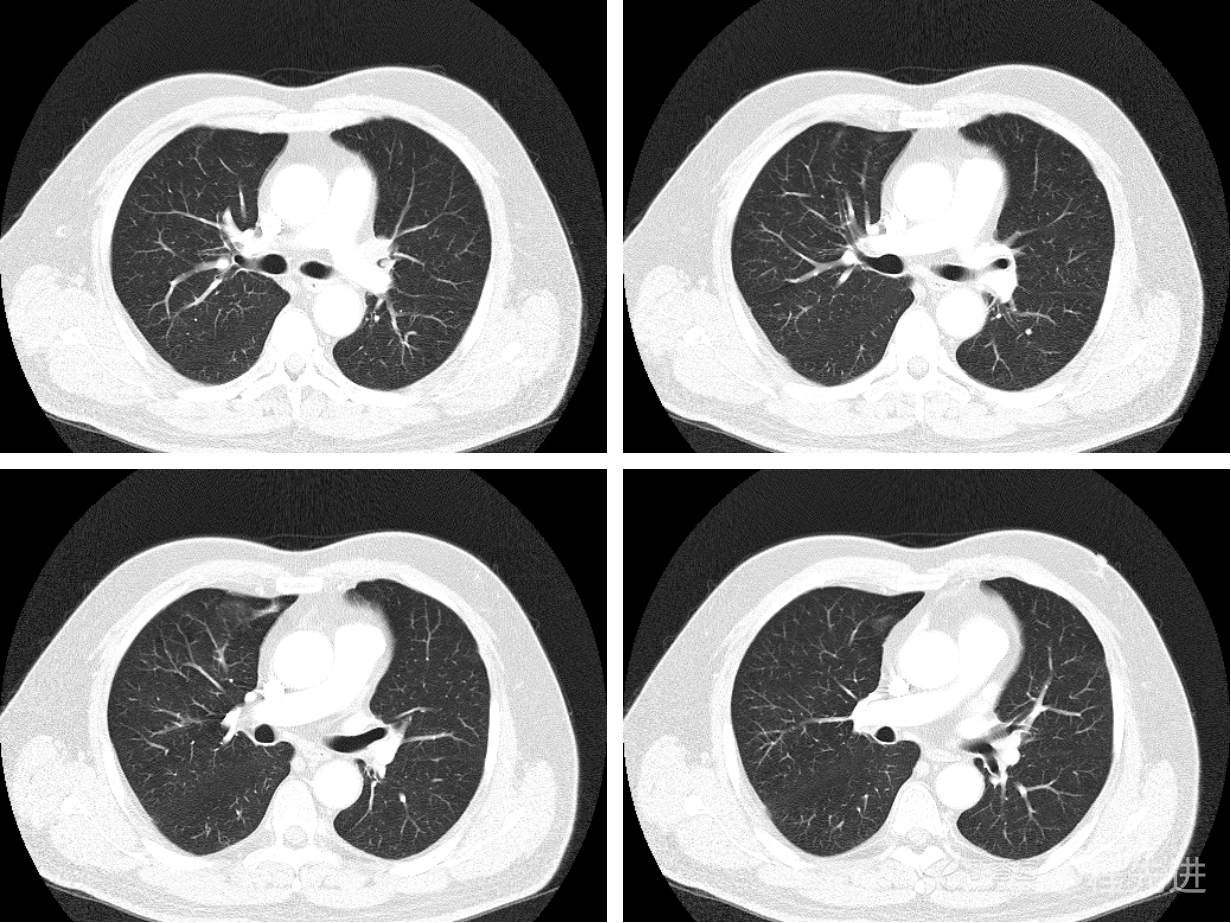

现病史概要:患者入院前约半月无明显诱因下出现咳嗽、胸闷症状,无明显发热症状,咳少量白痰,无明显咯血、喘息、头晕等不适,就诊我院查胸部CT示上纵膈肿物,左肺上叶支气管内肿物,现为行进一步治疗收入胸外科,患者近来饮食睡眠尚可,二便如常。